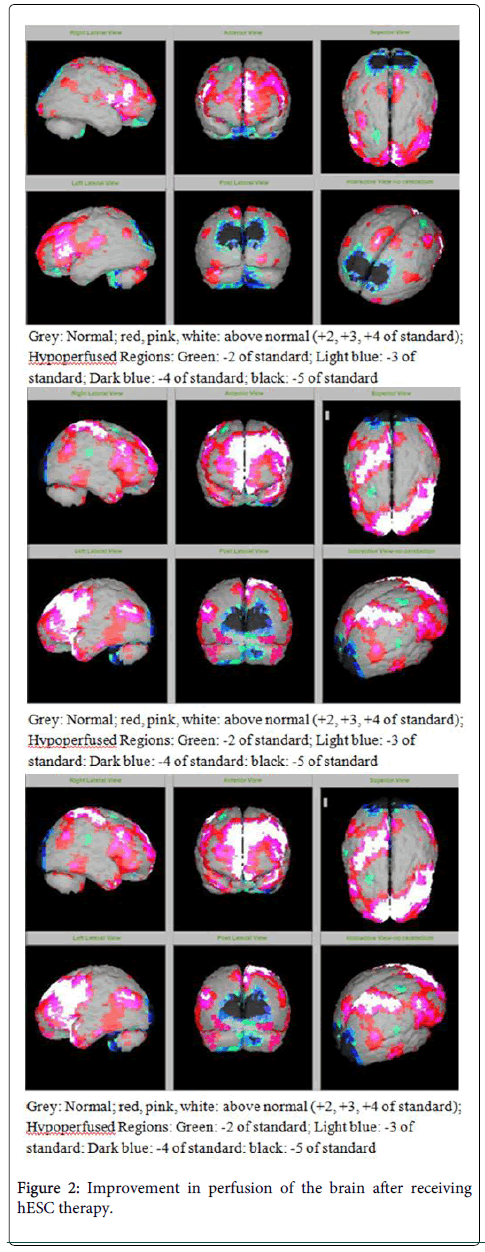

該患者的SPECT掃描如圖1和2所示。

SPECT掃描

在研究開始和結束時,23名患者接受了SPECT掃描。在枕葉或額葉或雙葉中觀察到灌注不足。23例接受SPECT掃描的患者中,5例患者表現為枕葉灌注不足,7例患者表現為額葉灌注不足,11例患者表現為枕葉和額葉灌注不足。

總體而言,治療結束時,2名患者的灌注正常,18名患者(12名男性和6名女性患者)顯示灌注顯著改善(>60%),3名患者顯示灌注中度改善(30-60%)。大多數在接受hESC治療前額葉和枕葉嚴重低灌注的患者在接受 hESC 治療后情況有所改善。23名可獲得SPECT掃描報告的患者的GMFCS評分在hESC治療后有所改善(表2)。

眾所周知,神經干細胞可以通過重新填充受損區域并防止細胞進一步退化來恢復正常視力。hESC通過增殖成相似的細胞類型來啟動受損細胞的再生。在本研究中觀察到灌注改善,這反映在SPECT掃描中。詹森等人研究顯示,一名5歲腦癱患者在接受臍帶血干細胞治療2個月后視力有所改善。